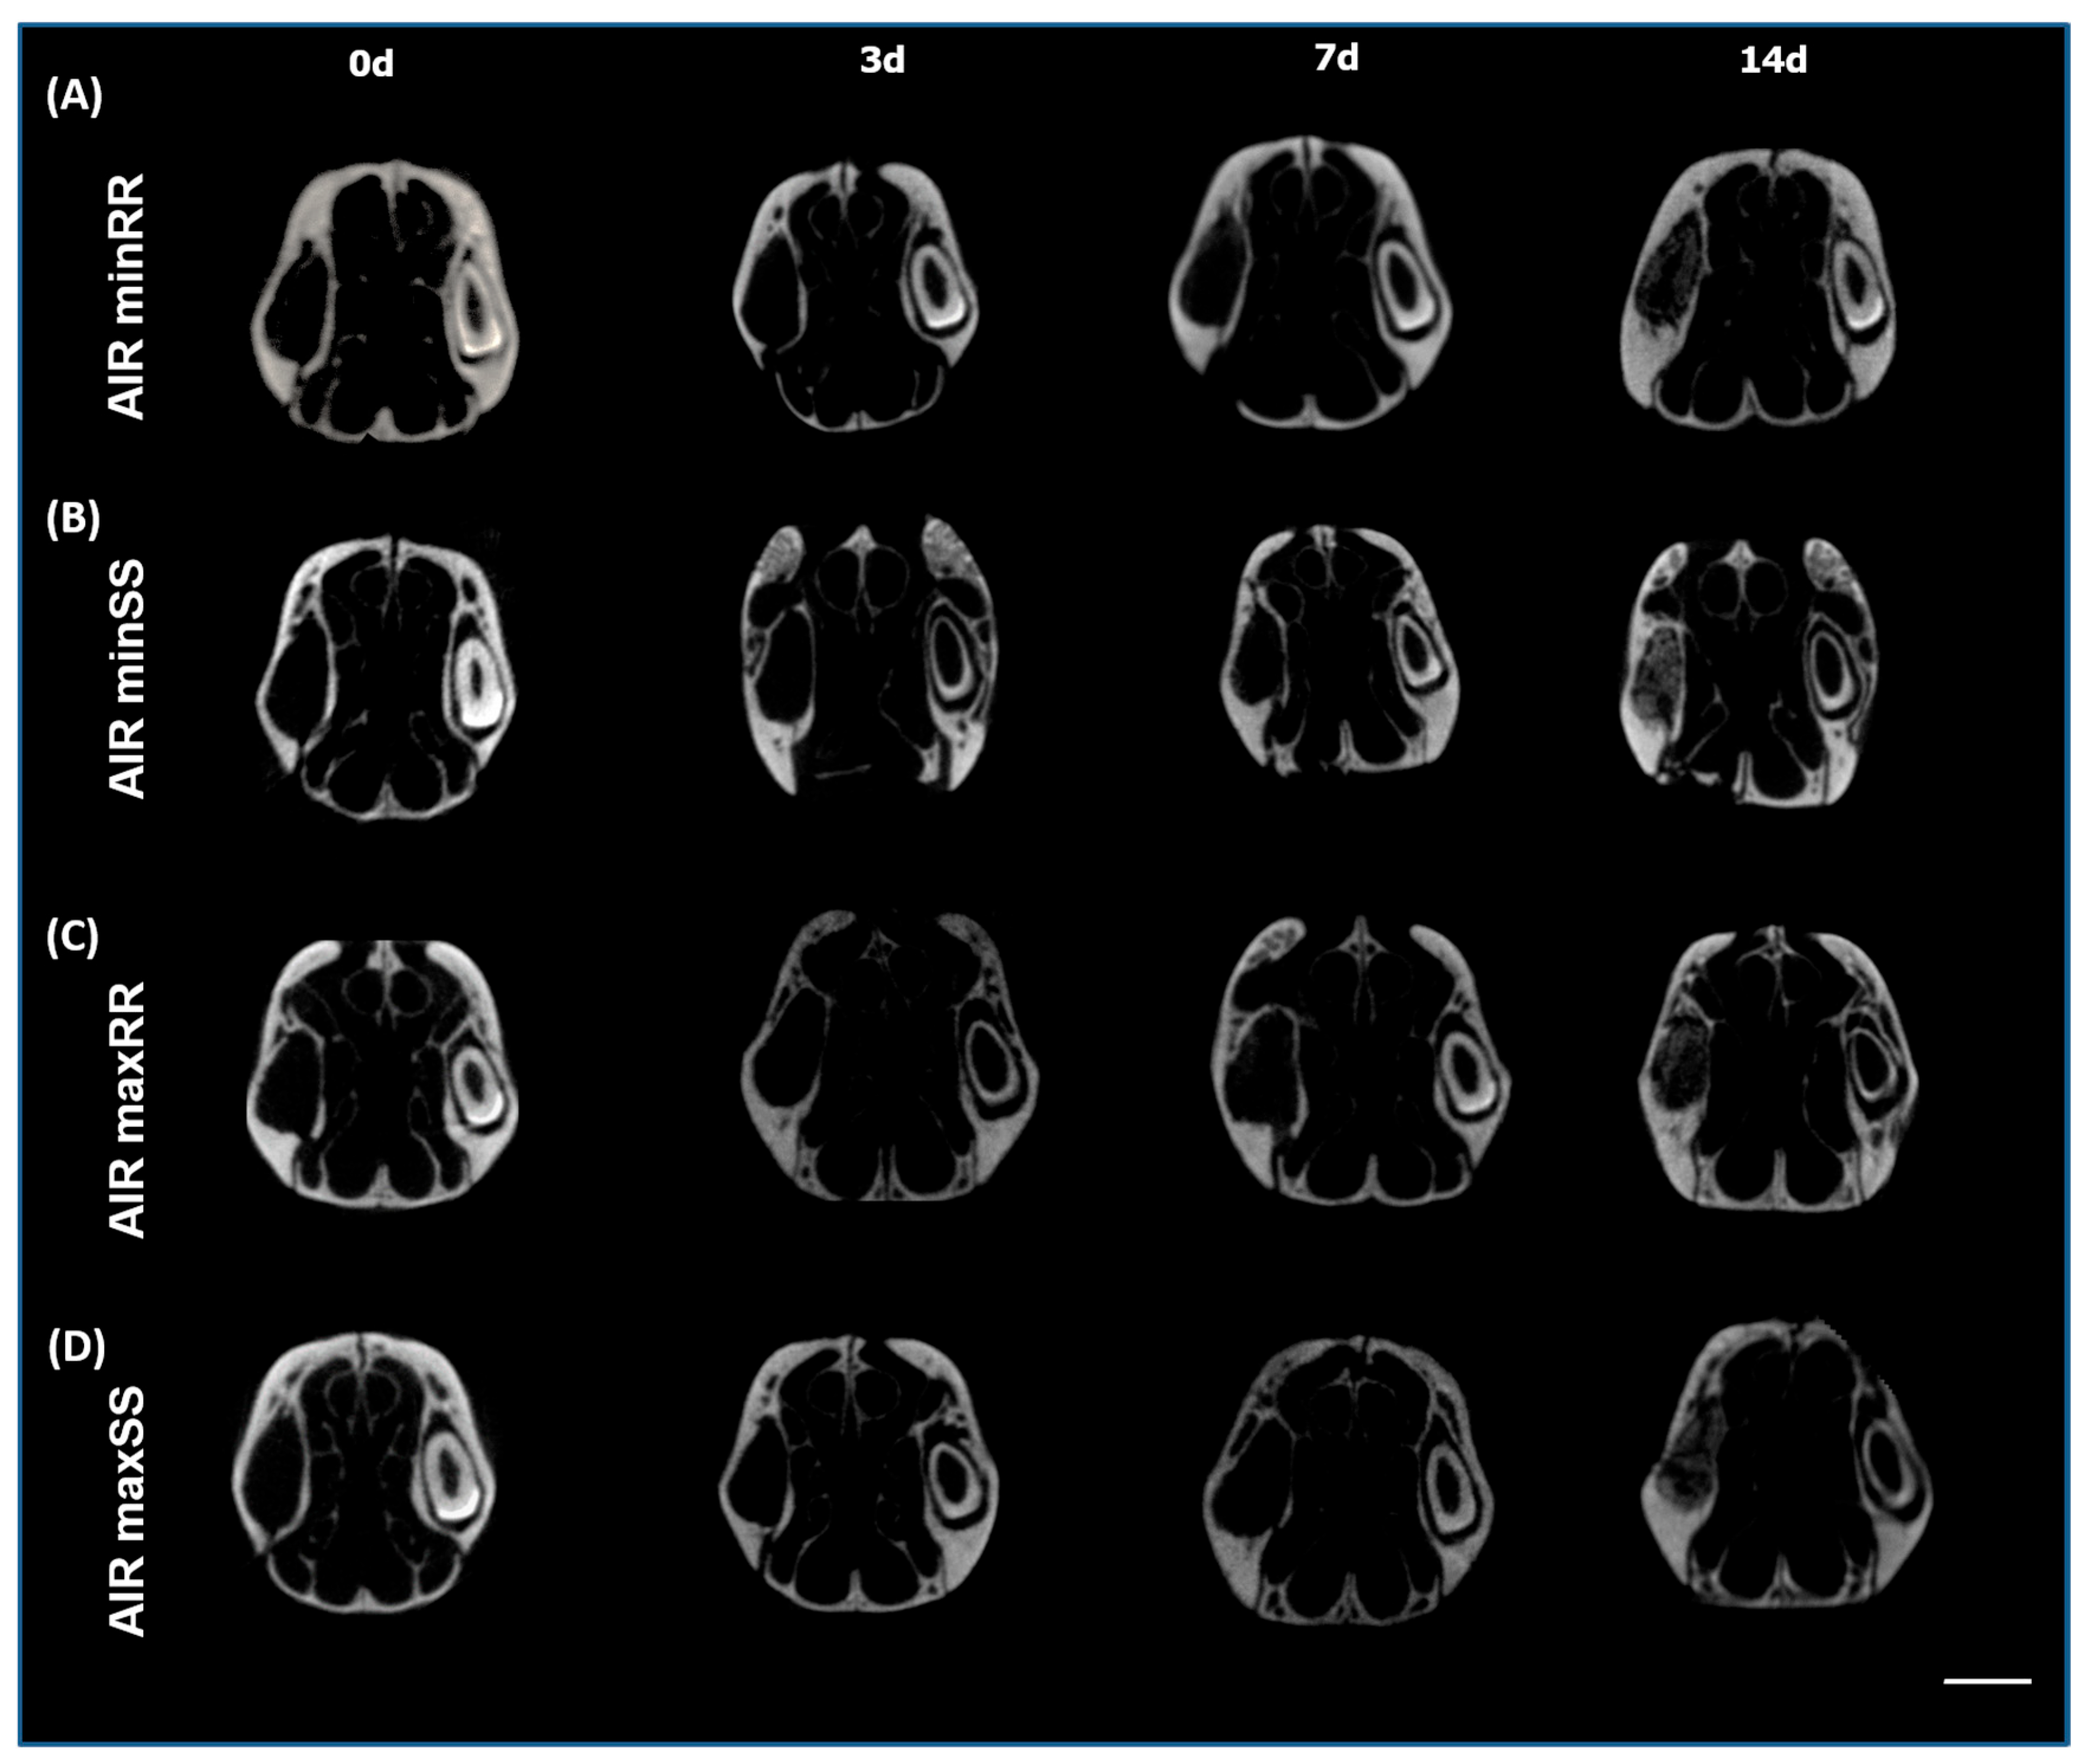

2.3. Micro-Computed Tomography (μCT) Assessment

3.1. Micro-Computed Tomography μCT Analysis